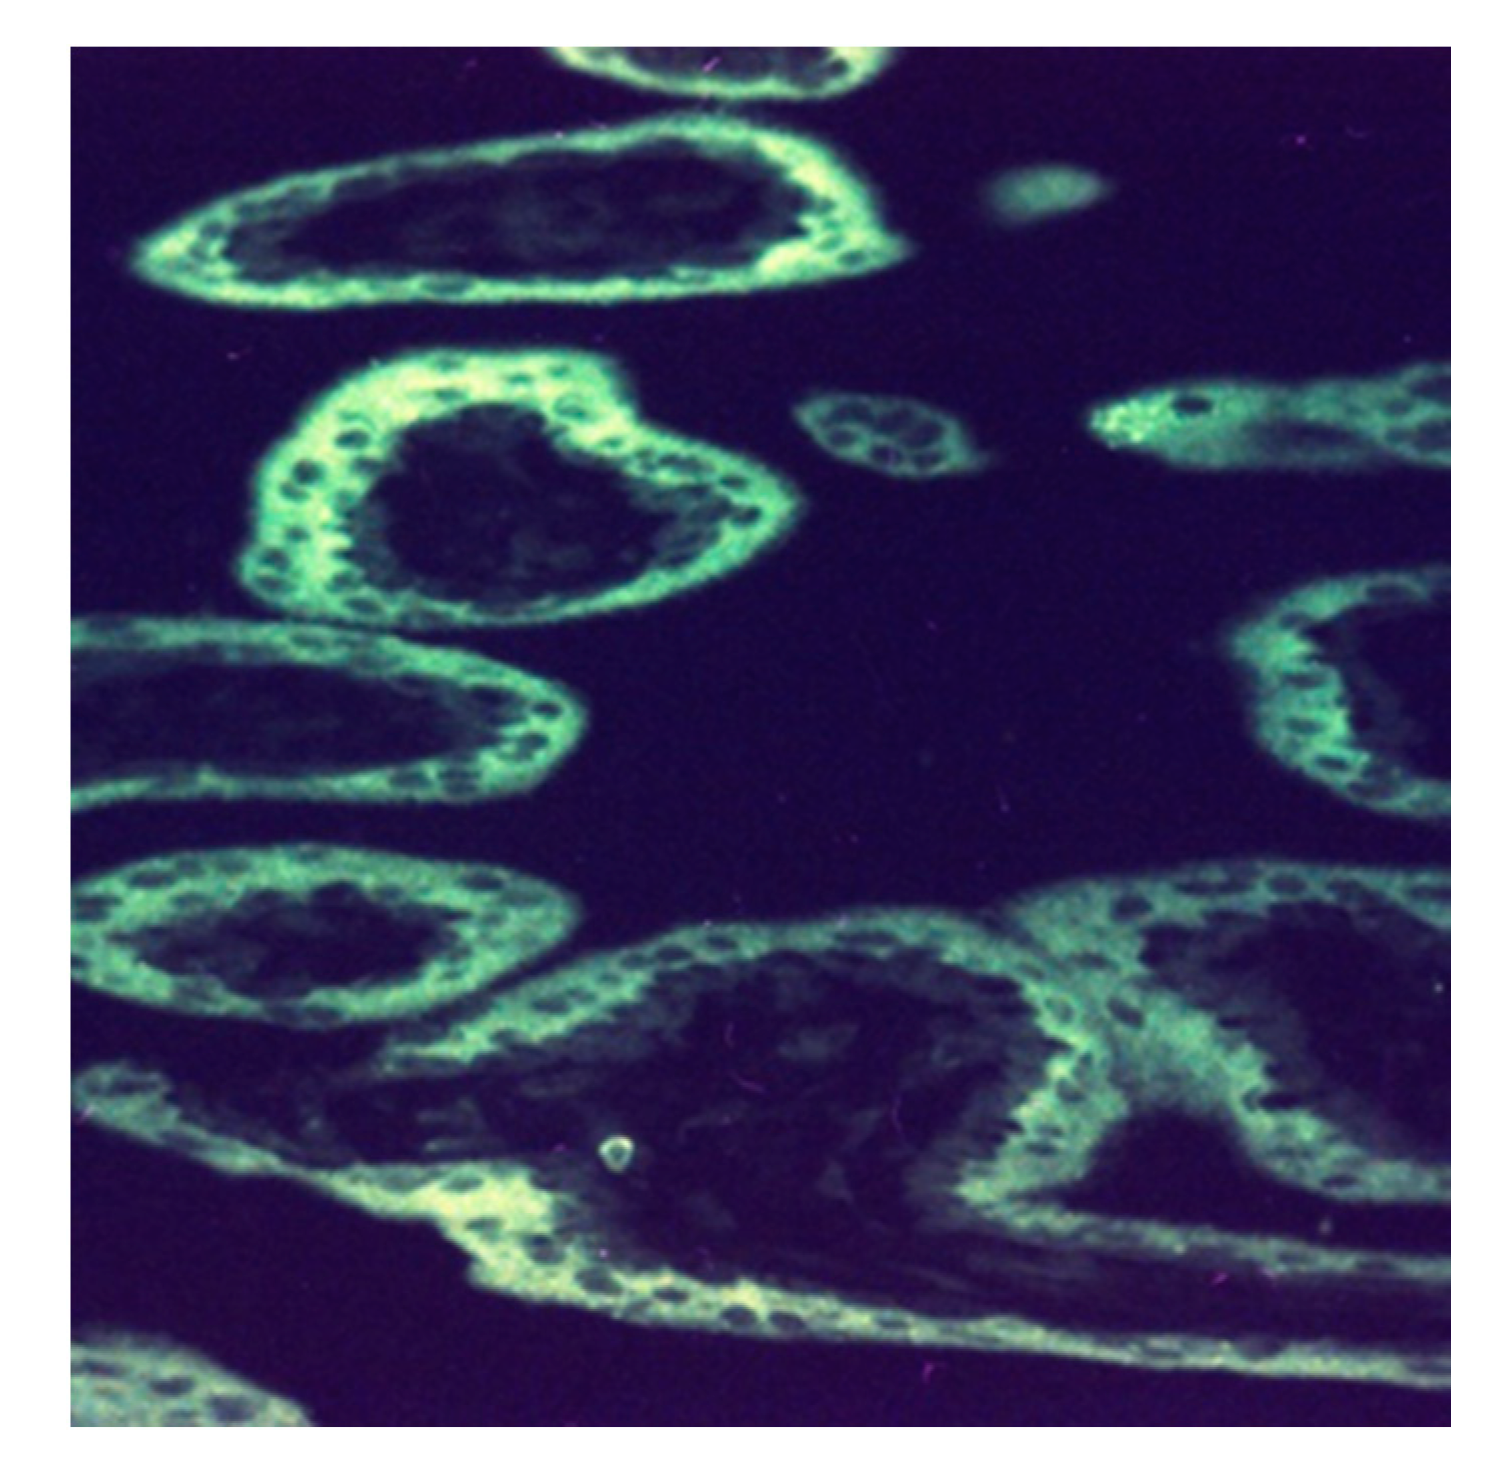

Figure 5. Human placental lactogen secretion from the syncytiotrophoblast at 12 w 2 d (×320). The fluorescent reaction with fluorescein-isothiocyanate (FITC)-labeled anti-hPL (rabbit) is confined to the syncytiotrophoblast layer of chorionic villi, thus creating the image of a “white ring”.

In the lacunar space, CV consisting of two layers of cells, differentiated from the trophoblast, projects in a dendritic shape toward the maternal side and makes contact points with the endometrium. The inner layer of CV is the actively proliferating cytotrophoblast, and the outer layer is formed from the syncytiotrophoblast, which erodes maternal tissues and anchors the villi to the endometrium. The syncytiotrophoblast plays the most important role in maintaining pregnancy by directly contacting the endometrium for gas exchange. It also secretes human placental lactogen (hPL) to absorb the nutrients, necessary for the fetus, from the mother (Figure 5); secretes hCG to maintain the corpus luteum graviditatis of the ovary; and regulates estrogen and progesterone secretion [29].